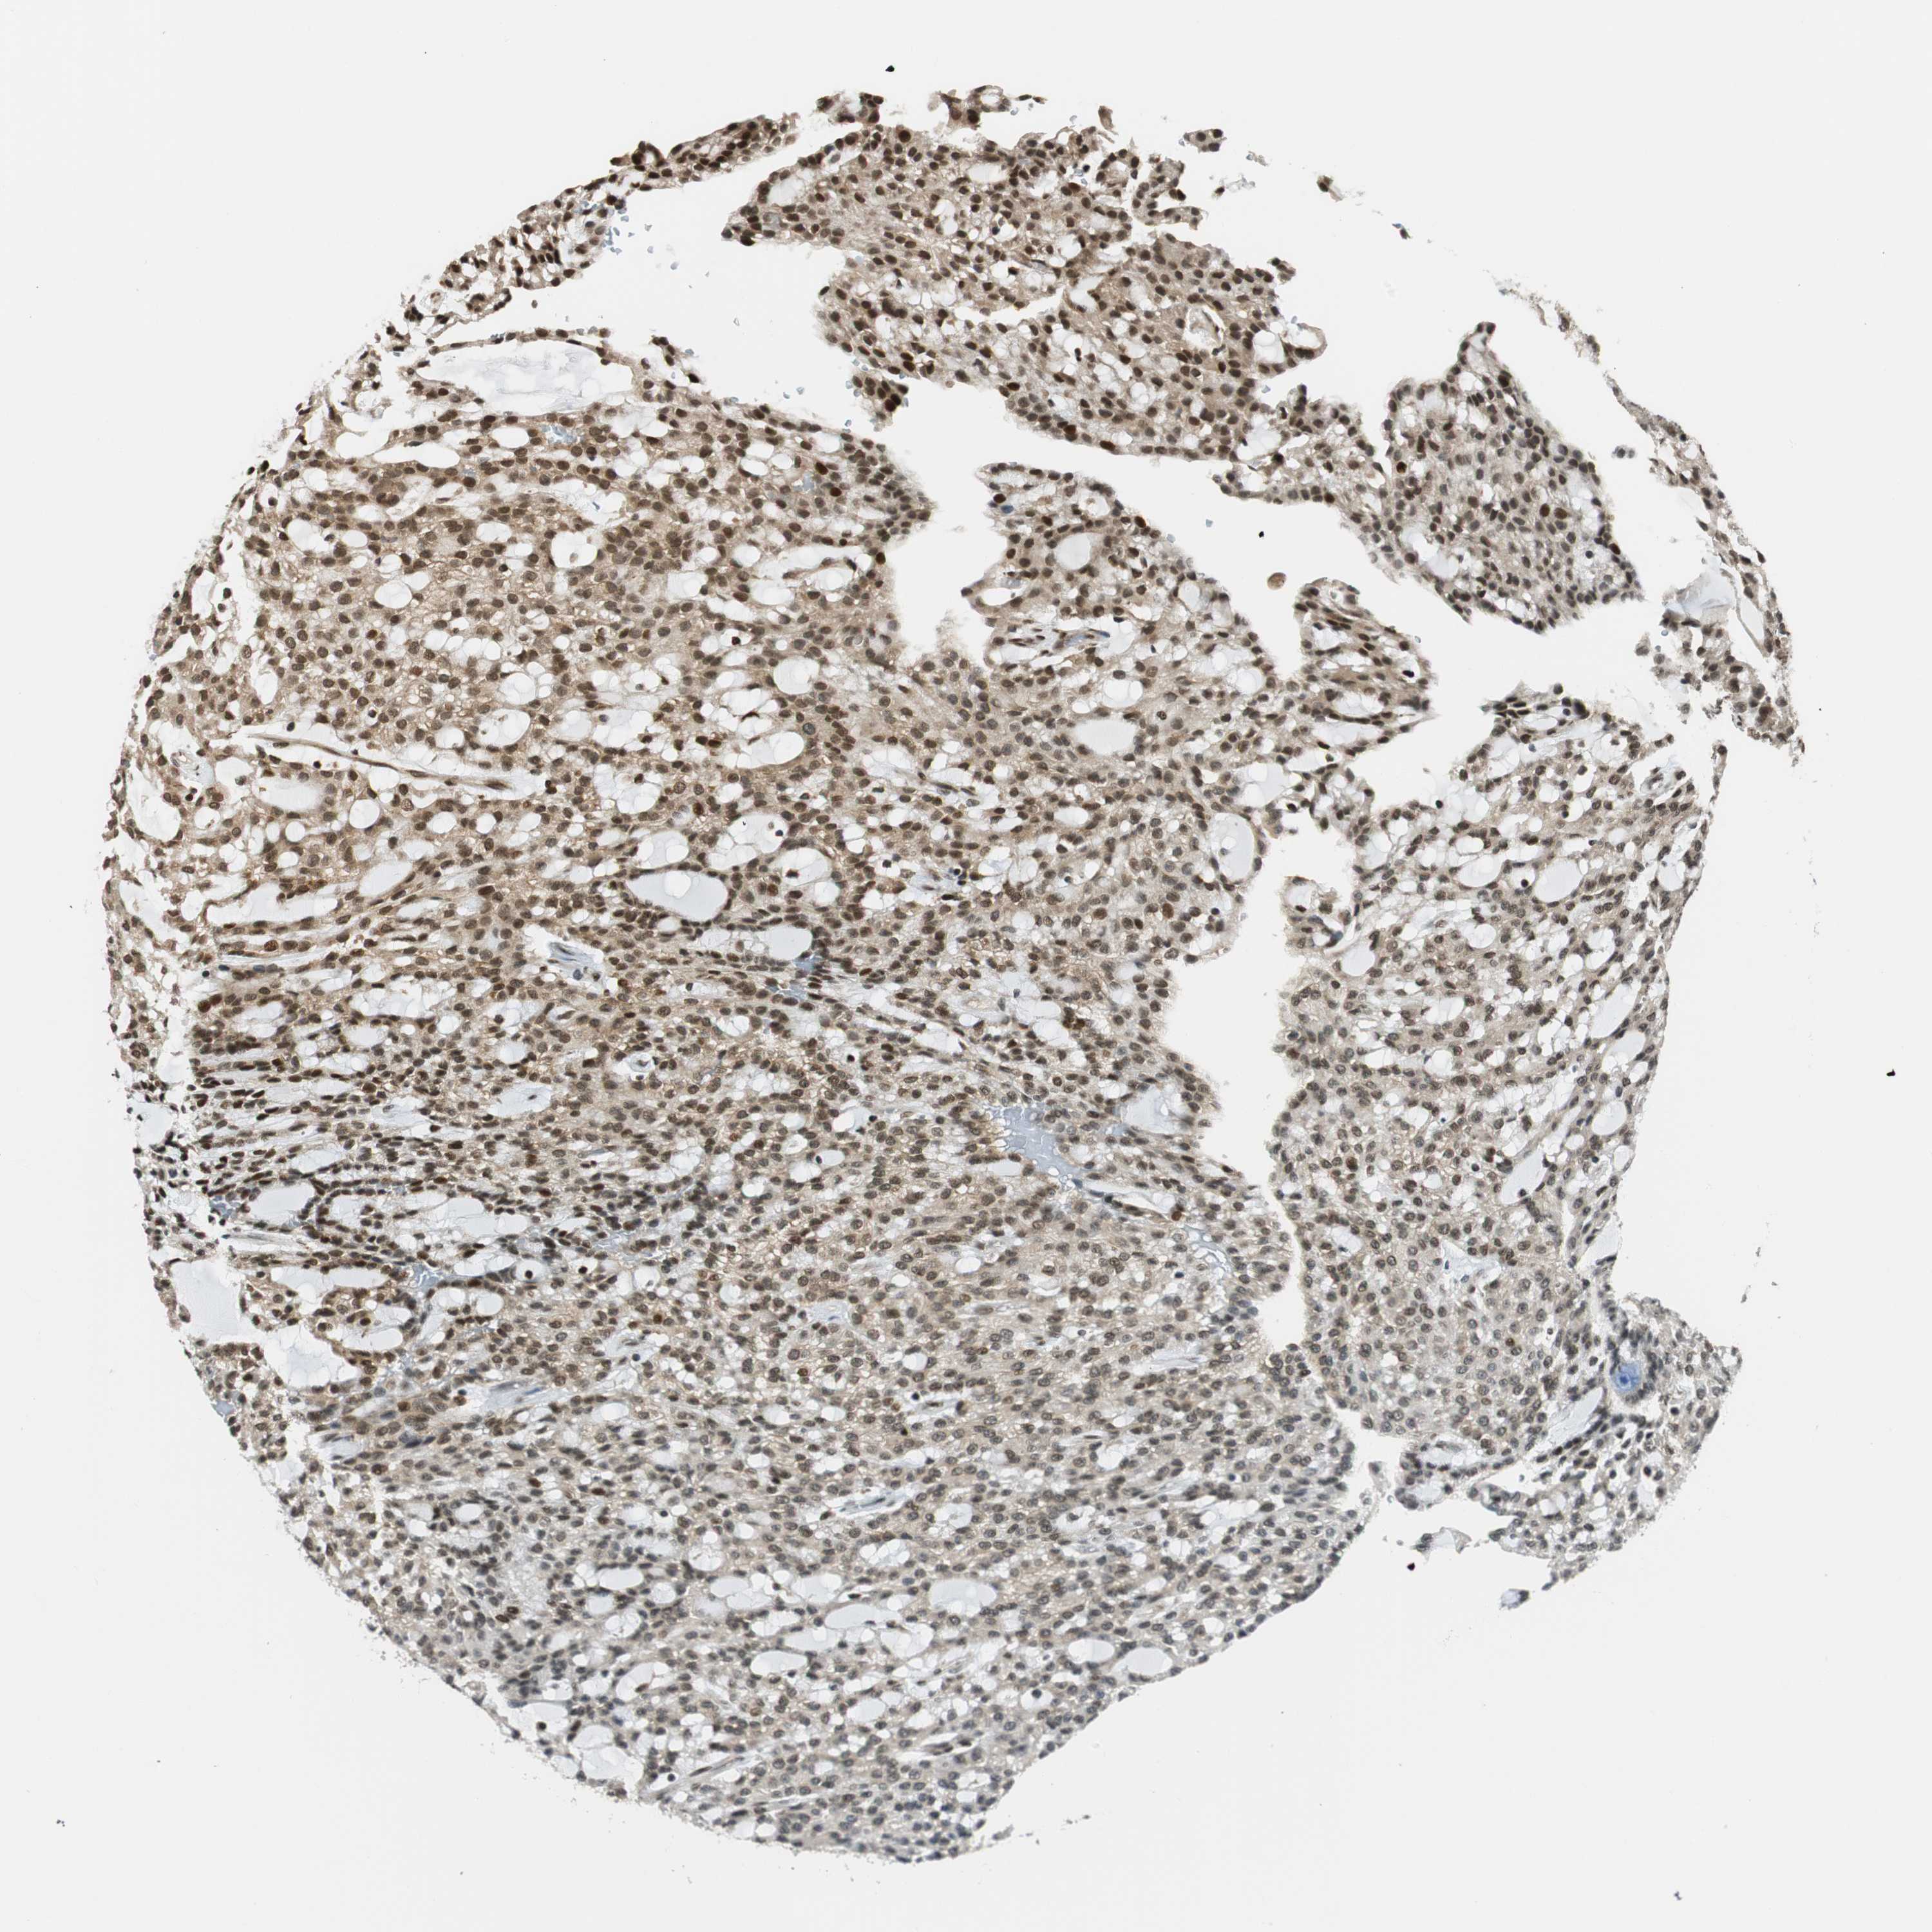

KIDNEY RENAL CLEAR CELL CARCINOMA (VALIDATION) - Interactive survival scatter ploti

The Survival Scatter plot shows the clinical status (i.e. dead or alive) for all individuals in the patient cohort, based on the same data that underlies the corresponding Kaplan-Meier plots. Patients that are alive at last time for follow-up are shown in blue and patients who have died during the study are shown in red.

The x-axis shows the expression levels (FPKM) of the investigated gene in the tumor tissue at the time of diagnosis. The y-axis shows the follow-up time after diagnosis (years). Both axes are complimented with kernel density curves demonstrating the data density over the axes. The top density plot shows the expression levels (FPKM) distribution among dead (red) and alive patients (blue). The right density plot shows the data density of the survived years of dead patients with high and low expression levels respectively, stratified using the cutoff indicated by the vertical dashed line through the Survival Scatter plot. This cutoff is automatically defined based on the FPKM cutoff that minimizes the p-score. The cutoff can be changed by dragging the vertical line or by entering a cutoff value in the square labeled "Current cut-off".

Under the Survival Scatter plot the p-score landscape (black curve; left axis) is shown together with dead median separation (red curve; right axis). Dead median separation is the difference in median mRNA expression between patients who have died with high and low expression, respectively. It is calculated as follows: median FPKM expression of dead patients with high expression - median FPKM expression of dead patients with low expression. This is intended to aid the user in visually exploring custom cutoffs and the associated p-scores and dead median separation.

Individual patient data is displayed and can be filtered by clicking on one or more of the category buttons on the top of the page. Categories describing expression level and patient information include: high, low, alive, dead, female, male and tumor stages. The scale of the x-axis can be toggled between linear and log-scale by clicking on the "x log" button. Mouse-over function shows TCGA ID, patient information and mRNA expression (FPKM) for each patient.

& Survival analysisi

Kaplan-Meier plots summarize results from analysis of correlation between mRNA expression level and patient survival. Patients were divided based on level of expression into one of the two groups "low" (under cut off) or "high" (over cut off). X-axis shows time for survival (years) and y-axis shows the probability of survival, where 1.0 corresponds to 100 percent.

RING1 is not prognostic in Kidney Renal Clear Cell Carcinoma (validation)

: 28.79

Average pTPM 31.4

Number of samples 100